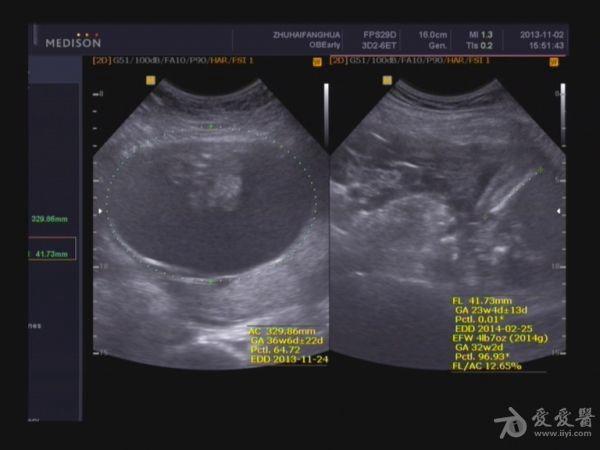

本帖最后由 jlslst 于 2013-11-2 21:06 编辑 女 25岁,中期孕胎儿产前超声筛查,超声所见:BPD:53mm(22w+1d), H C:212mm(23w+2d),A C:329mm, F L:38mm(23w+0d),HUM:不清,AFD:14mm,AFI:38mm,

单胎妊娠;臀位,颅骨环基本完整,脑中线居中,CER: 24mm,CM:不清,双侧丘脑可见,侧脑室未见明显扩张,小脑可显示欠清,胎儿颈项部欠清,胎儿颜面显示不清,胸腔增大内见积液,腹壁完整,肝、可见,腹腔内大量积液,最大径约:71mm,胸腔内积液最大径:11.4mm,胃及膀胱显示不清。双肾显示不清。双侧四肢长骨显示欠清。

胎盘:附着于子宫后壁,厚度44mm,成熟度:0级,范围面积大,几乎覆着全后壁。

诊断意见: 1.宫内中期孕,单胎,胎儿存活,

(根据头围及股骨超声孕周约:22w+3d、胎儿体重约:1256g±)

2.胎儿畸形,胸、腹腔大量积液,

3.超大胎盘,羊水少。